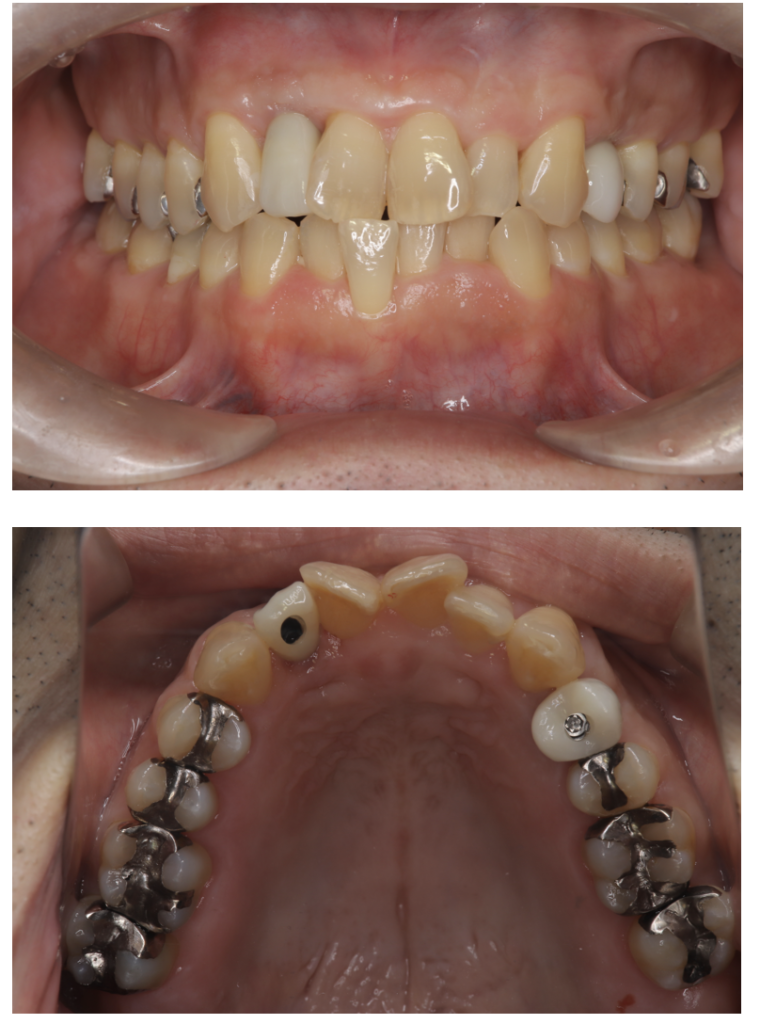

インプラント 1 No.1

Before

After

| 備考 | 院長より 残すことが難しい状況になった歯を抜いて、インプラントを2本埋入しました。 骨もしっかりとあり良い状況です。まだまだこれから長い間使って頂けると思います。 |